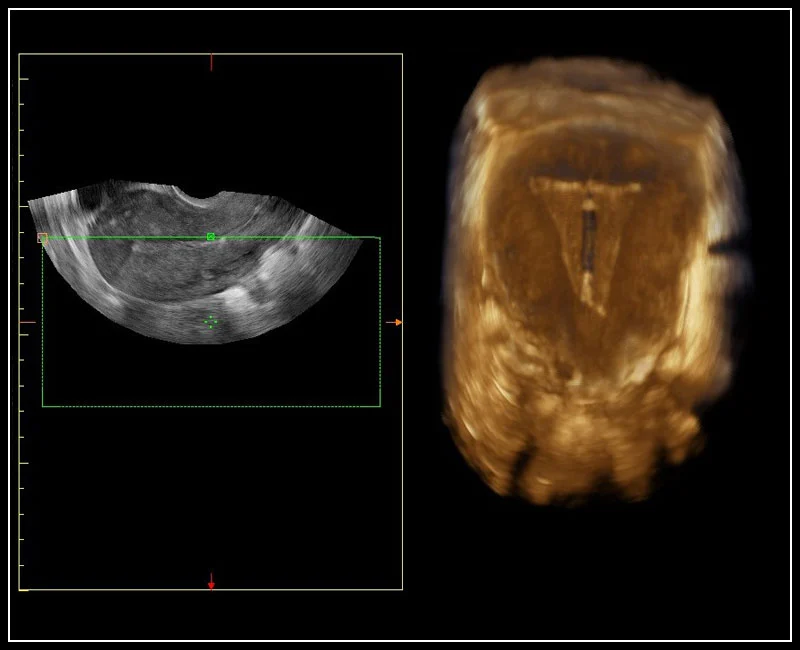

MyLab™Sigma - Semi transparent rendering of fetal spine

MyLab™Sigma - Semi transparent rendering of fetal spine